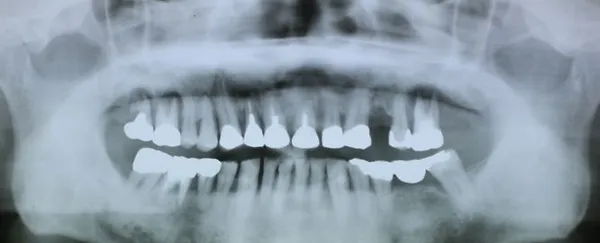

6入れ歯にしないブリッジ治療【ケース3】

このケースの患者さんは上の歯の歯槽膿漏が心配で来院されました。上の歯は11本残っており、下の写真の緑色に囲われた歯を1本抜歯して、計10本の歯を使って端から端まで繋げる治療を行いました。H22.5月に治療が始まり、H23.1月に完成しました。

H22.5のレントゲン